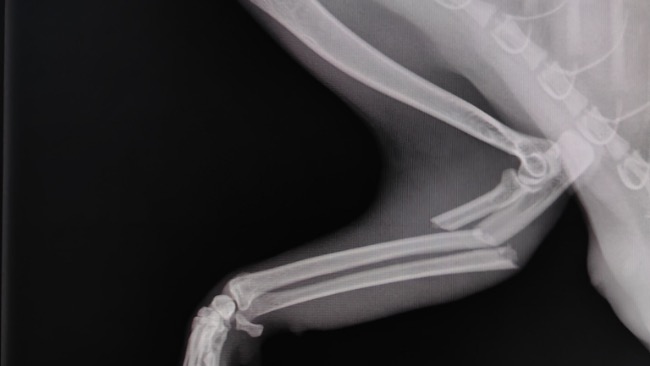

Zamiast chodzić – skakała. I już wiedziałyśmy, że to nie zwykła „dziwna maniera”. Diagnoza zmroziła nas: połamane dwie przednie łapki. Maleństwo nie może się poruszać, leży pod kroplówkami, wycieńczone, bez apetytu, w inwazji pcheł i wszołów… Sutki nabrzmiałe, z których leci mleko – a więc gdzieś tam czekały na nią kocięta, które nigdy nie dostaną swojej mamy z powrotem.

Operacje obu łap to ogromny koszt, którego nie jesteśmy w stanie pokryć. Ledwo udało nam się uregulować poprzednie faktury, a długi wciąż ciążą nad nami. A teraz przed nami kolejne wyzwanie – życie tej kotki zależy od pieniędzy, których po prostu nie mamy.